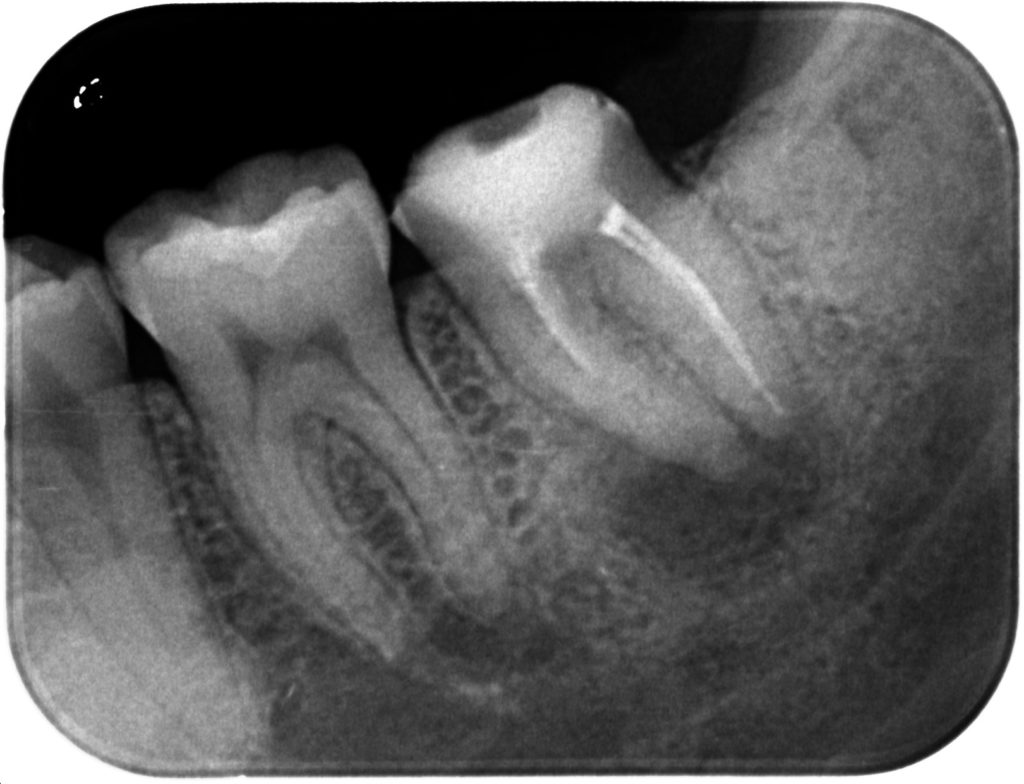

噛むと痛い。根っこの中の病気って??

2019年10月24日

北戸田COCO歯科 副院長田口です最近はめっきり寒くなり、秋らしくなってきましたね 寒いけど、コートを着るか着ないか迷うくらいのこの季…[read more]